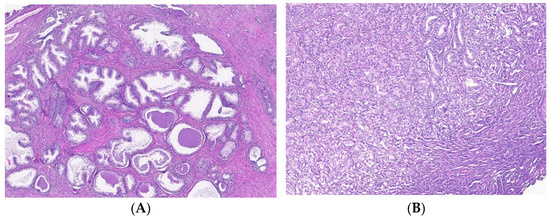

2.2. Morphological Evaluation of Tissue Samples